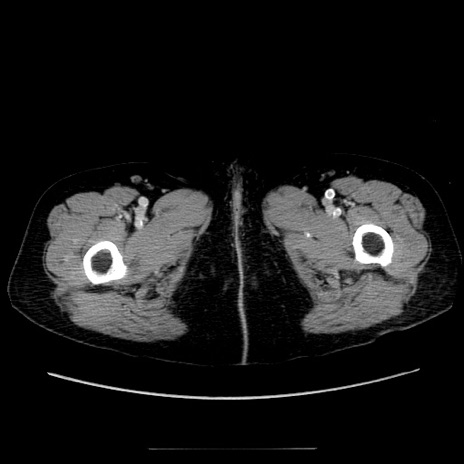

症例5(横断像)

【症例】70歳代女性

【主訴】お腹が張る

【現病歴】1週間くらい前から腹部膨満の自覚あり。昨日夜から増悪したため、本日救急外来受診。

【身体所見】意識清明、BT 36.5℃、BP 165/106mmHg、HR 80bpm、SpO2 98%、腹部:膨満、軟、自発痛・圧痛なし、触診にて不快感あり、腸蠕動音:減弱

【データ】WBC 12600、CRP 1.04